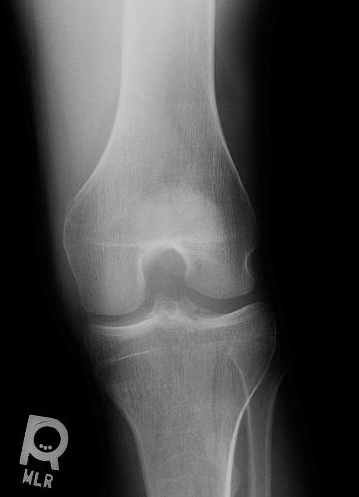

KNEE - AP RADIOGRAPH

When there is an intraarticular fracture of the tibial plateau or of one of the femoral condyles, bone marrow (mostly fat) migrates from the marrow space into the joint space. With fracture, blood also escapes, and a lipohemarthrosis is produced. Fat is less dense than blood, and it layers superior to it, producing the change in radiographic density referred to as a fat-blood interface (FBI sign).

CASE 1: These four radiographs are from a 50 year old male who fell 1 day prior to presentation. There is a tibial plateau fracture and a lipohemarthrosis. Click on each image for a larger view and notice the location of the fat-fluid level.